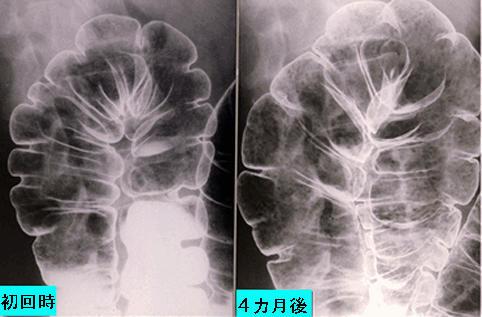

Multiple Lymphomatous Polyposis type malignant lymphoma of the large intestine followed up for several times.

Malignant Lymphoma/MLP type

Location

Technique, Method

1 - 9